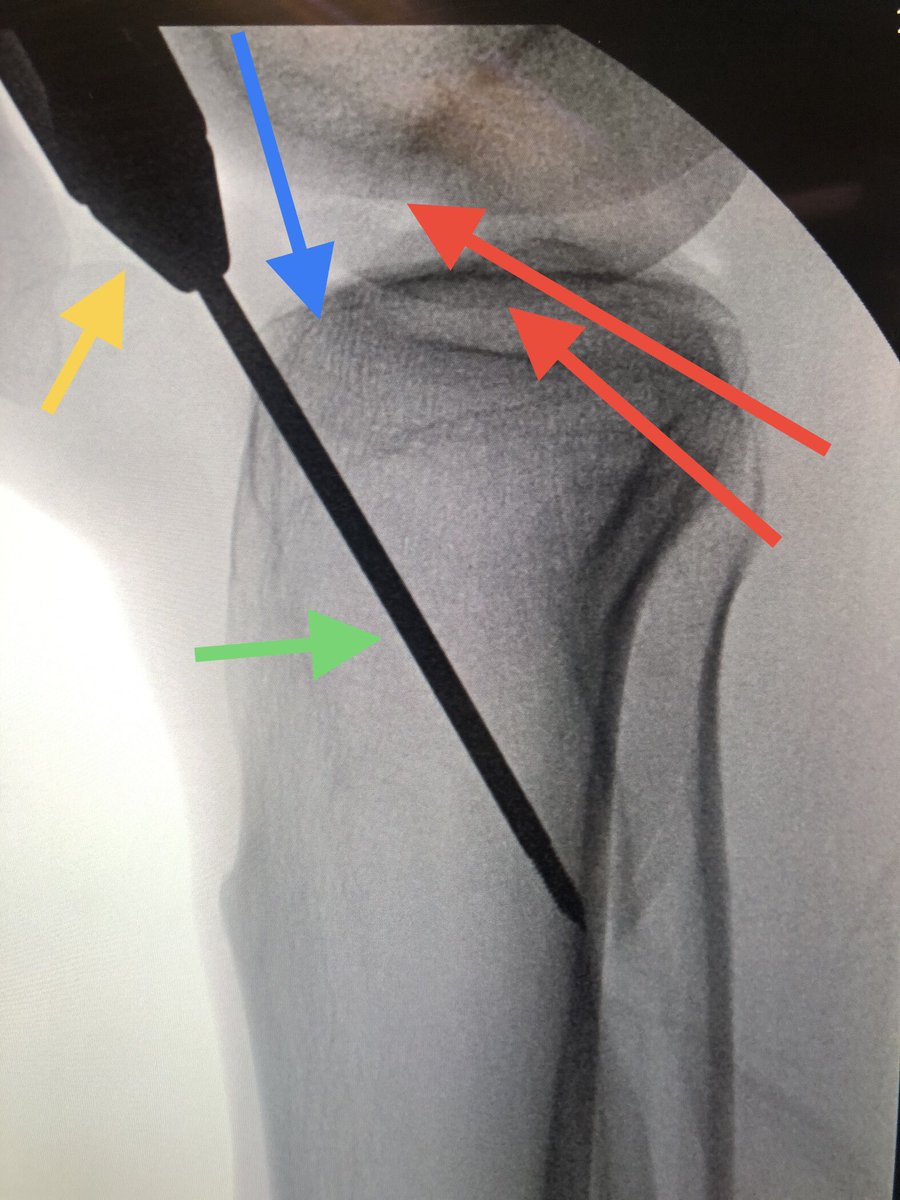

👉🏻 9-years old .

❓Who would go for surgery and who would not ? Is there sth that you don’t like / accept and want to correct ?

#orthotwitter #paeds_